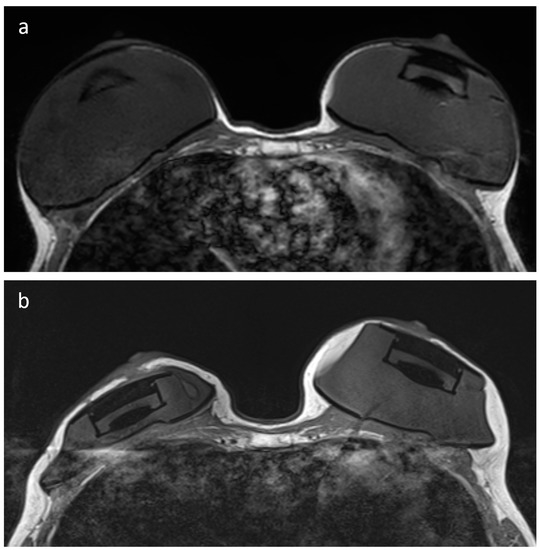

- Maximum diameter of the artifact caused by the RFID port on axial T1-weighted images (on the side with largest artifact in patients with bilateral expanders) and maximum diameter of the expander on the same axial plane, with calculation of their ratio.

- Maximum diameter of the RFID-related artifact.